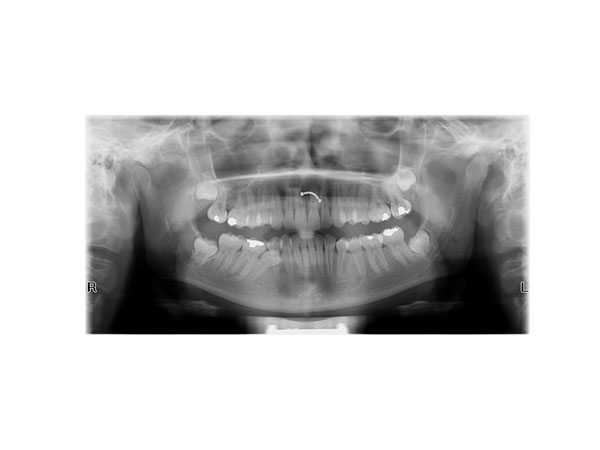

We perform all types of dental, jaw, sinus, and cervical vertebrae imaging, with the following three types being the most requested:

• Orthopantomogram (digital panoramic X-ray of the entire jaw)